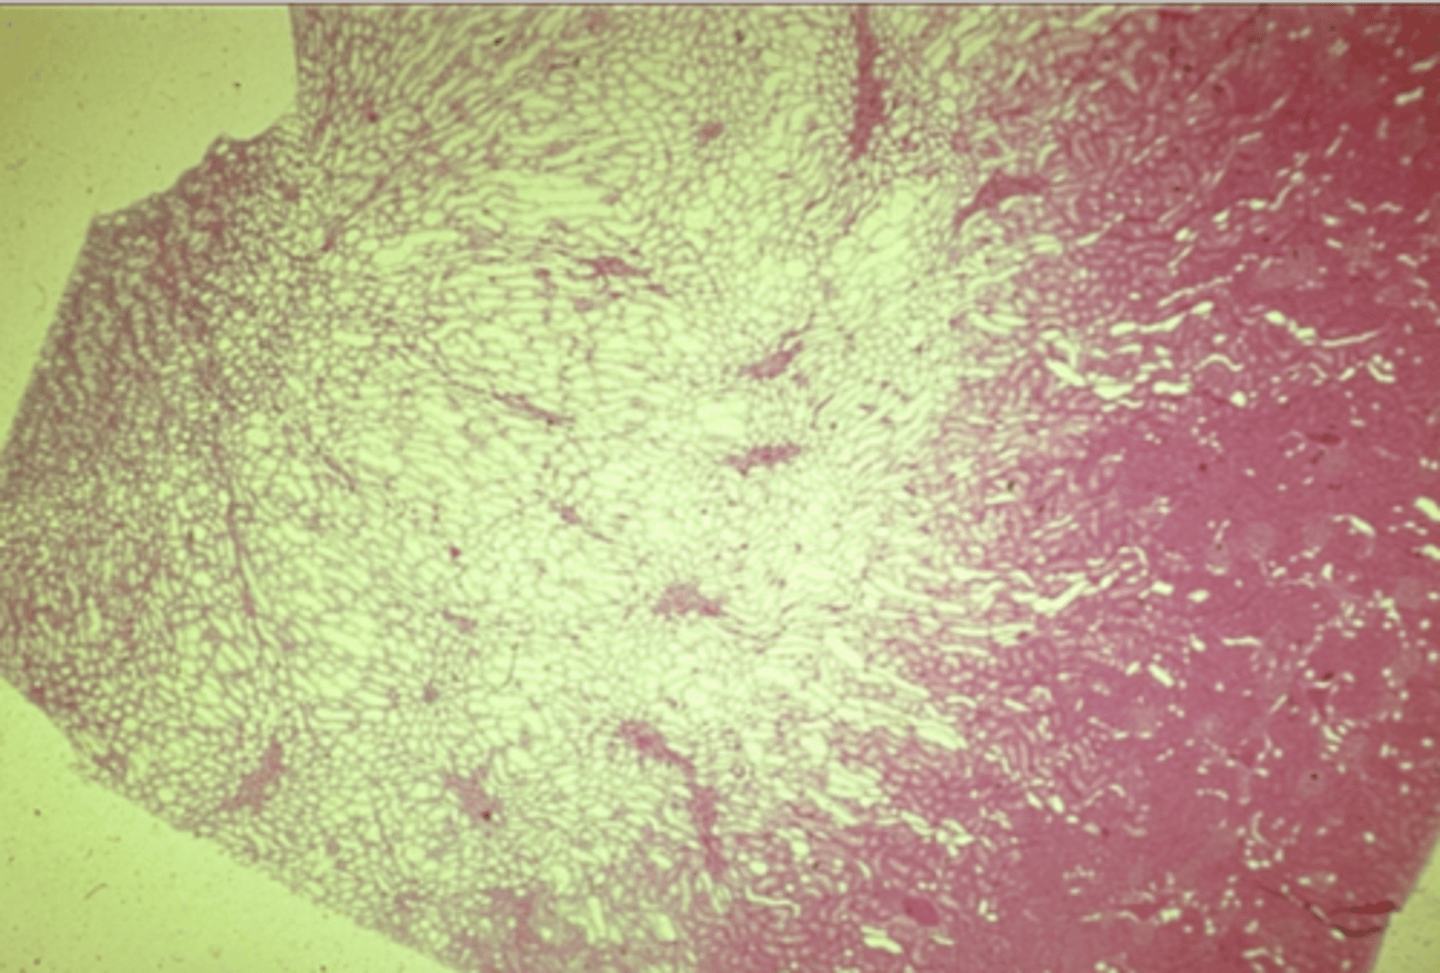

Kidney

What is this?